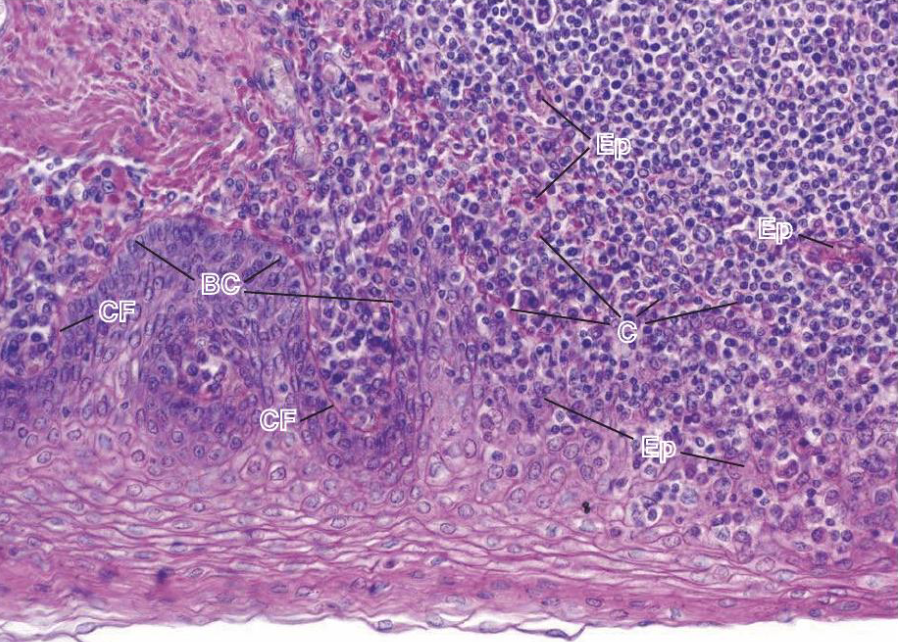

Amígdala de humano

N - Nódulo linfático

S - submucosa

CG - centro germinativo

Ly - linfocitos